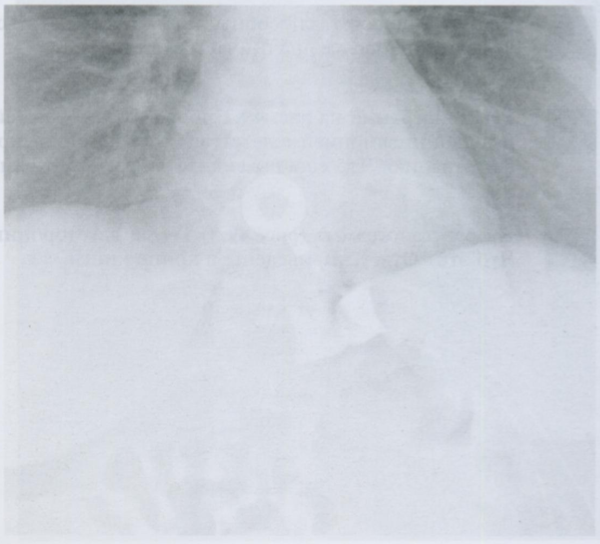

На данной карточке обратите внимание на просветления, отмеченные стрелками, которые свидетельствуют о наличии свободного воздуха в мягких тканях и средостении.

Признаки пневмомедиастинума:

1) эмфизема мягких тканей шеи

2) заметное просветление по контуру сердца или аорты, ограниченное снаружи париетальной плеврой (это то, что видно на данном снимке)

3) субкардиальное или ретрокардиальное скопление воздуха, четкая визуализация диафрагмы на всем протяжении

4) вилочковая железа у детей обнаруживается в виде «треугольного паруса» (у новорожденных - это норма)

5) пневмоторакс

6) пневмоперикард

7) воздух, окружающий ствол легочной артерии (в виде круга в боковой проекции)

На снимках воздух вдоль контуров сердца + воздух между волокон грудных мышц